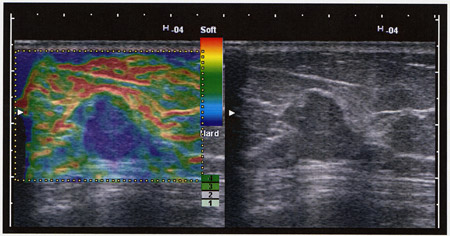

エラスト機能は,超音波探触子と呼ばれるセンサ部分を生体に接触させ,わずかに圧迫を繰り返すだけで,リアルタイムに組織の硬さをカラーで画像化する技術。探触子を押したときに生じる生体の歪みが,柔らかい部分では大きく,硬い部分では小さいという現象を利用している。

Real-time Tissue Elastographyの画像例 |